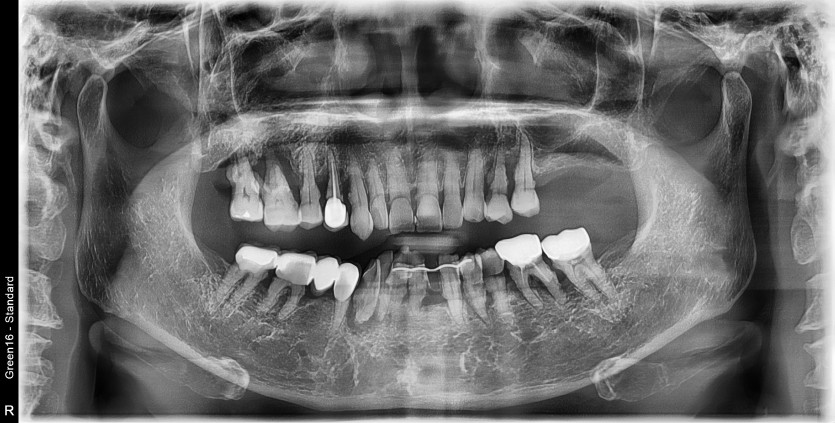

만 61세 전체 임플란트 증례

전체 임플란트 증례입니다.

18개의 임플란트로 완성하였습니다.